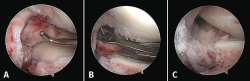

Figure 4. Arthroscopy views from the anterolateral portal, showing bone avulsion with a fragment of the medial root (A), suture advancement through the meniscal root (B), and bone avulsion reduced in its bone bed (C).

Arthroscopy confirmed the diagnosis by visualizing the avulsed root and bone fragment at medial level (Figure 4A) and the radial lesion of the external root (Figure 5). Palpation of both roots evidenced clear instability. The ACL was greatly affected, with subtotal rupture, while the PCL presented correct stability in response to palpation and testing.

The medial root avulsion fracture was repaired using a standard transtibial pullout technique(1,3,6). Suturing required the use of no. 2 FiberWire® (Arthrex, Naples, FL, USA ) through the root with the Knee Scorpion™ system (Arthrex, Naples, FL, USA) (Figure 4B). A FlipCutter® III retrograde reamer (Arthrex, Naples, FL, USA) with a Unicorn Meniscal Root (UMR) guide (Arthrex, Naples, FL, USA) was used to drill a blind tibial tunnel, 6 mm in diameter and 15 mm in length, from the bone bed of the medial meniscus towards the anteromedial tibial cortical layer. The meniscus sutures were retrieved through the trans-bone tunnel with a FiberStick® (Arthex, Naples, FL, USA). The suture was knotted through a metal button, securing correct reduction of the meniscal avulsion (Figure 4C).

The rupture of the lateral meniscal root was repaired with two U-shaped meniscal sutures using a Knee Scorpion™ suture passer. Lastly, reconstruction of the ACL was carried out with an anterior tibial tendon allograft with proximal and distal cortical suspension fixation according to the all-inside technique, avoiding the coalition of tunnels at tibial medial level.